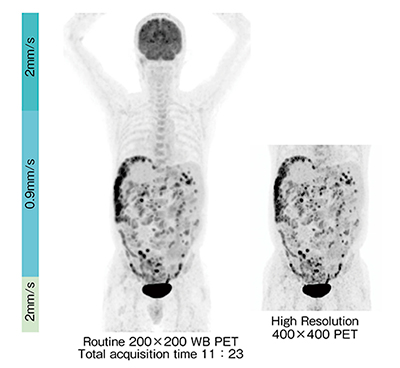

FM法では,1回の全身撮像データを用い,病変の描出に適した任意の再構成範囲と条件を用いることにより,読影医の必要に応じた画像を撮像後のデータから作成することができる。図2の症例では,1回の撮像から,通常マトリックス画像と腹部の高マトリックス画像を再構成した。高マトリックス画像は,点在する病変の描出が優れており,これらの画像は約11分半の撮像データから追加撮像なしに得ることができた。図3に示す上行結腸がんの肝転移症例では,撮像時間6分程度で,全身画像および呼吸同期画像の双方を得ることができた。従来法では,追加撮像のために検査時間の延長が懸念される呼吸同期撮像であるが,FM法と組み合わせることにより,全検査において呼吸同期信号を収集しておき,後処理の一部として必要に応じて呼吸同期再構成を行うという臨床手技が実用的に可能となった。

図2 多発性腹膜播種

高マトリックスで細かな病変が描出される。

(画像ご提供:慶應義塾大学病院様)